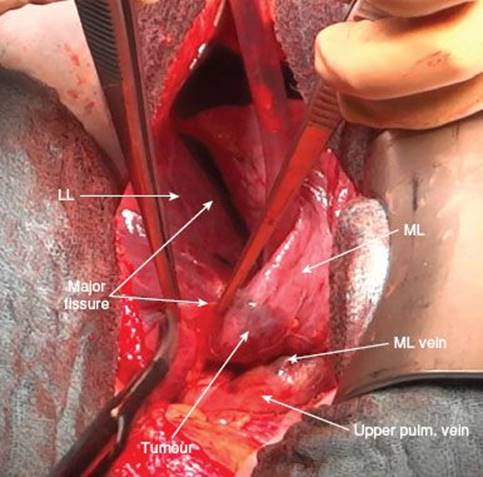

Sometimes tumors in the upper or the lower lobe invade the interlobium thereby infiltrating the middle lobe. In these cases an upper or lower bilobectomy (upper or lower lobe as well as the middle lobe) is indicated. The same holds true in case of infiltration of the interlobar artery in lower lobe tumors or lesions at the origin of the lower lobe bronchus, because the middle lobe bronchus is often located just opposite of the bronchus of segment 6 (apical segment of lower lobe).

The following description will be detailed for the open approach but it is basically true for the thoracoscopic approach as well. When performing the procedure by VATS one should have a low threshold to convert to the open technique in cases of impaired visualization or complications. Because the vessels to the middle lobe come from the interlobar artery and drain into the upper pulmonary vein respectively, insufficient visualization may lead to accidental transection or disrupture of vessels of the upper or lower lobe. This would result in additional lobectomy, in the worst case even in right-sided pneumonectomy.

However, as there are mostly more than one middle lobe arteries, complete visualization of all arterial branches is recommended. Therefore, the middle lobe is now placed anteriorly exposing the major fissure.

Dissection in the interlobium (Fig. 11.8) will lead to the interlobar part of the pulmonary artery which is usually found at the confluence of the major and minor fissures. The visceral pleura is held up with a DeBakey forceps and incised by electrocautery or Metzenbaum scissors. In this area there is rarely a complete bridging of lung parenchyma, so dissection can be carried down to the artery which presents itself again as a yellowish structure. Here, lymph nodes of station 11 are lying on top of the interlobar artery and as soon as they are lifted up the wall of the vessel becomes visible.